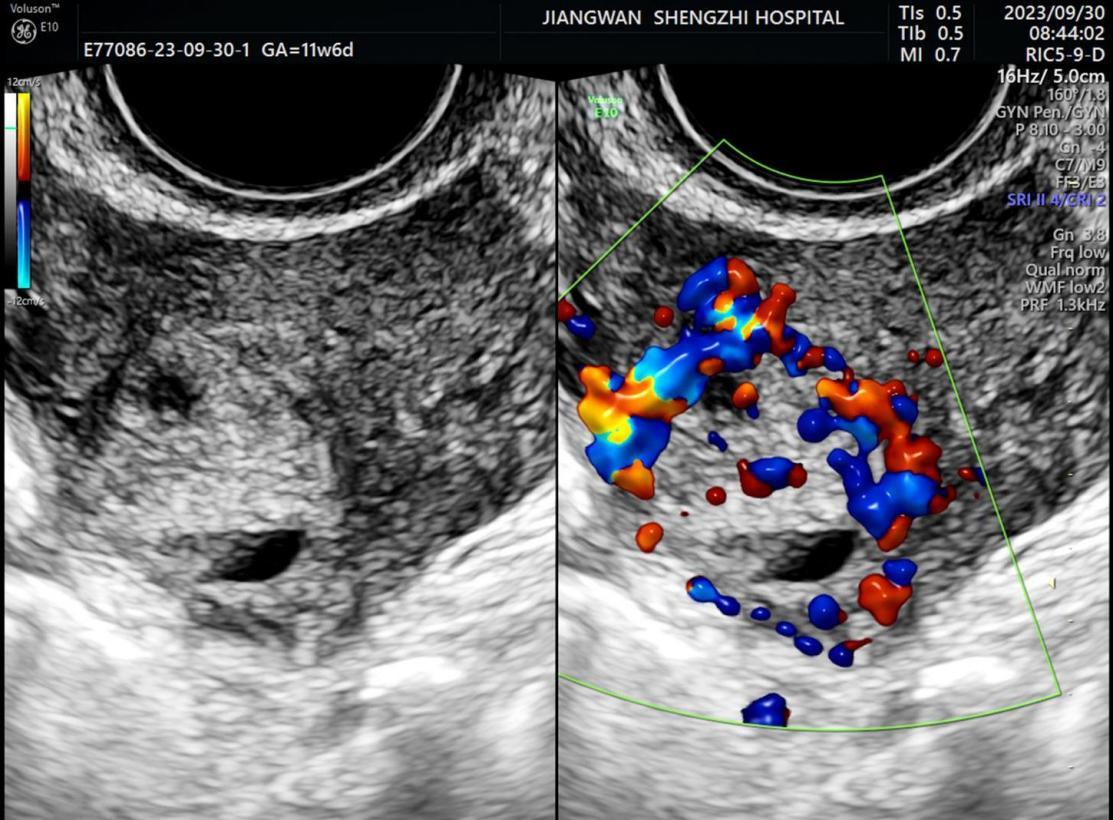

医生接诊后马上为何女士完善相关检查,超声科张白玉医生为她行彩超检查,图像显示:子宫宫底部偏右侧(似与右侧宫角相连)可见一范围约22X17X21mm的混合回声区,边界不清,形态不规则,内回声杂乱,CDFI:周边及内可见丰富的五彩镶嵌的血流信号。

二维超声图像